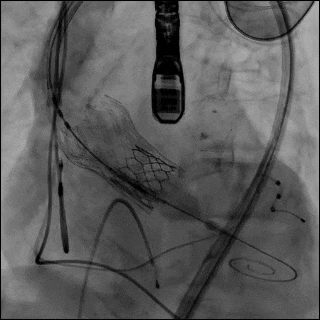

图6 逐步操作过程

(A)使用 21 mm TRUE balloon 行主动脉瓣预扩张。于钙化的 Evolut R valve 瓣叶水平可见明显“球囊腰征”(白色箭头),提示充盈过程中存在显著阻力。(B)植入 23 mm SAPIEN 3 Ultra RESILIA valve(S3UR)过程中发生球囊破裂。球囊远端可见造影剂积聚(白色箭头),形成类似“伞状”外观,提示存在水平撕裂。23 mm 瓣膜未完全释放(白色箭头)。(C)对侧入路行髂动脉造影。可见左侧髂总动脉夹层,但无活动性造影剂外渗(白色箭头)。(D)使用 23 mm TRUE balloon 对未完全扩张的 S3UR 瓣膜进行后扩张。(E)血管内干预后髂动脉造影。将 16F eSheath 回撤至左侧髂外动脉,并于夹层的髂总动脉内植入一枚 8 × 59 mm VBX 覆膜支架(白色双向箭头)。(F)血管内干预后股动脉造影。左侧股总动脉穿刺通路采用 7 × 50 mm Viabahn stent graft 进行封闭(白色双向箭头)。最终造影显示无造影剂外渗,血流通畅。

随后采用23 mm TRUE 球囊对未完全扩张的 S3UR 瓣膜行后扩张(图6D,视频9)。后TEE提示瓣膜位置良好,无瓣周漏(PVL)。

将16F鞘管回撤至左髂外动脉水平,并植入一枚8×59mm VBX 覆膜支架用以修复左侧髂总动脉夹层(图6E,视频10和11)。左股动脉穿刺口采用7×50mm Viabahn 覆膜支架进行封闭(图6F,视频12)。最终造影示无造影剂外渗,血流通畅(视频13)。